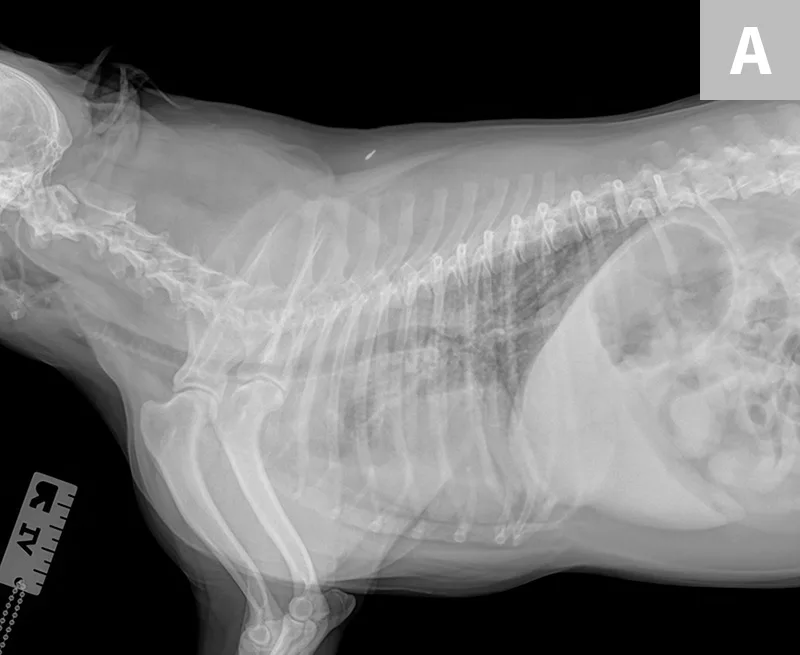

Thoracic radiographs (Figure) show an alveolar lung pattern in the ventral aspect of the right middle lung lobe that is most consistent with aspiration pneumonia or bronchopneumonia. Hemorrhage, neoplasia, and bronchial obstruction are also on the differential list but are considered less likely. Hepatomegaly is present, as is radiographic evidence of possible palate/pharyngeal region swelling and aerophagia.

FIGURE Right lateral (A), left lateral (B), and ventrodorsal (C) thoracic radiographs of the patient. Palate/pharyngeal region swelling can be observed (Barrow), as can an alveolar lung pattern in the ventral aspect of the right middle lung lobe (Carrow), which is most consistent with aspiration pneumonia or bronchopneumonia.